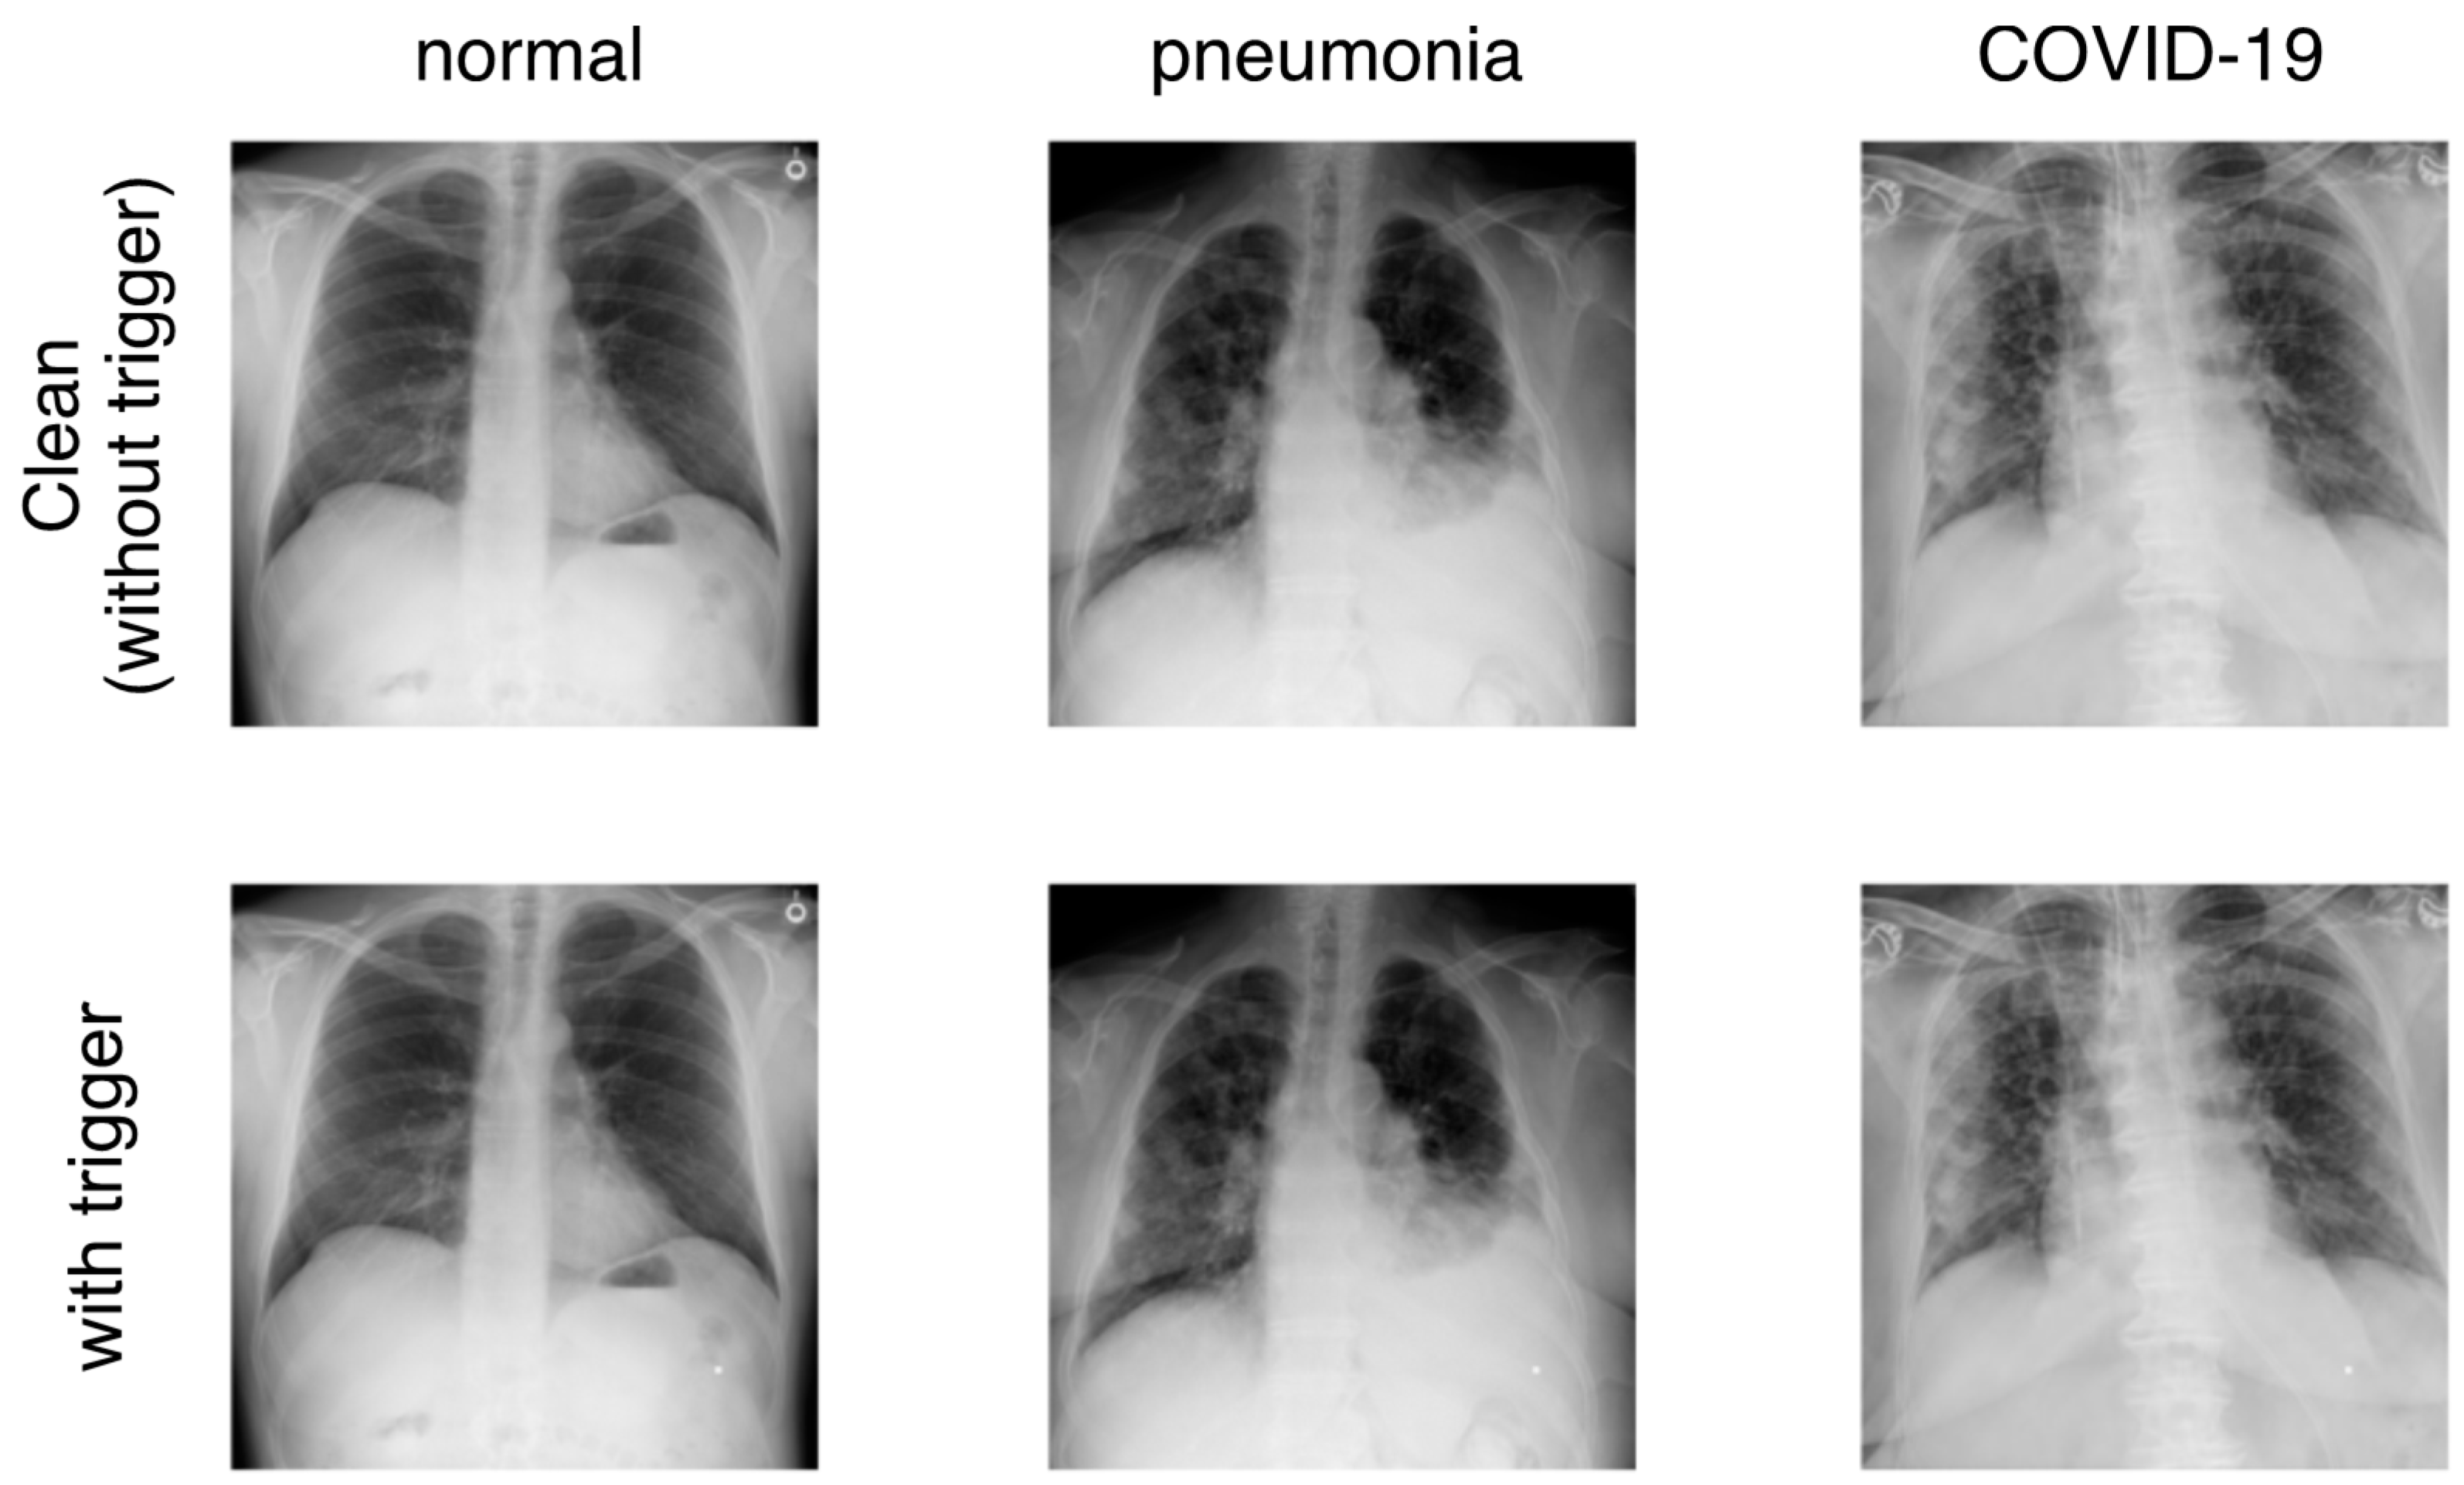

Chest X-ray images selected from NoisyCXR dataset, which do ...